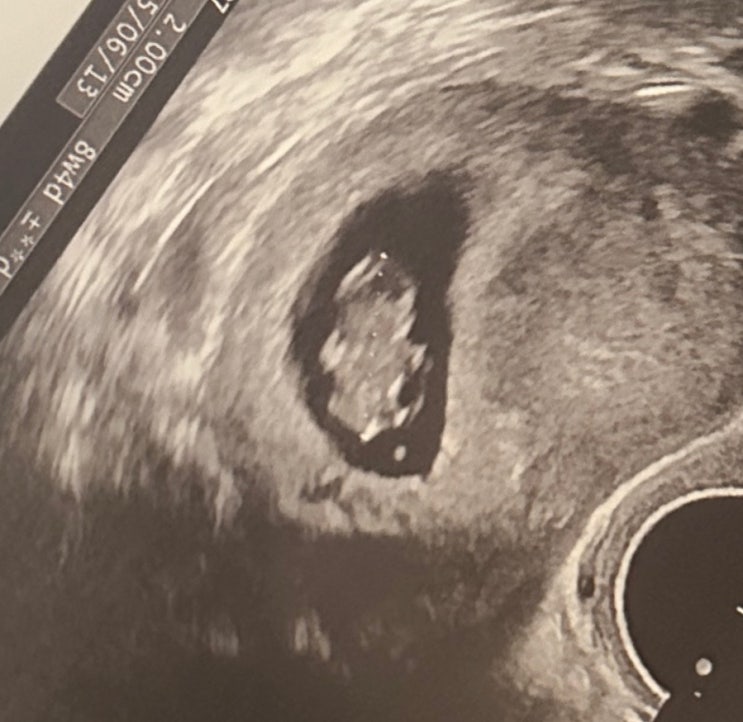

[임신기록] 다낭성 시험관 현대해상 태아보험 가입 후기 (내돈내산)

임신 10주차! 드디어 태아보험 가입 끝! 나는 시험관 임신이라 혹시 주사약때문에 제약이 있을까봐 9주차에...

[임신기록] 시험관 임신 / 6주~9주차 일상 / 난임병원 졸업

?️ 6주차 단축근무를 위해 팀에 임신사실을 공개했다. 눈치보였지만.. 나만 생각하기로한다?? 보...